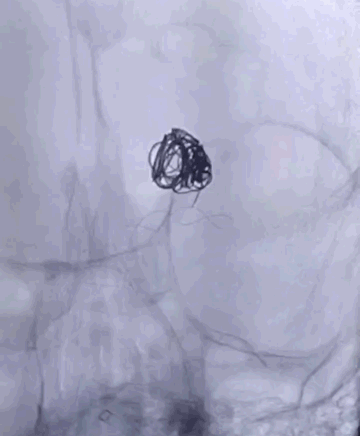

Tubridge Case 2